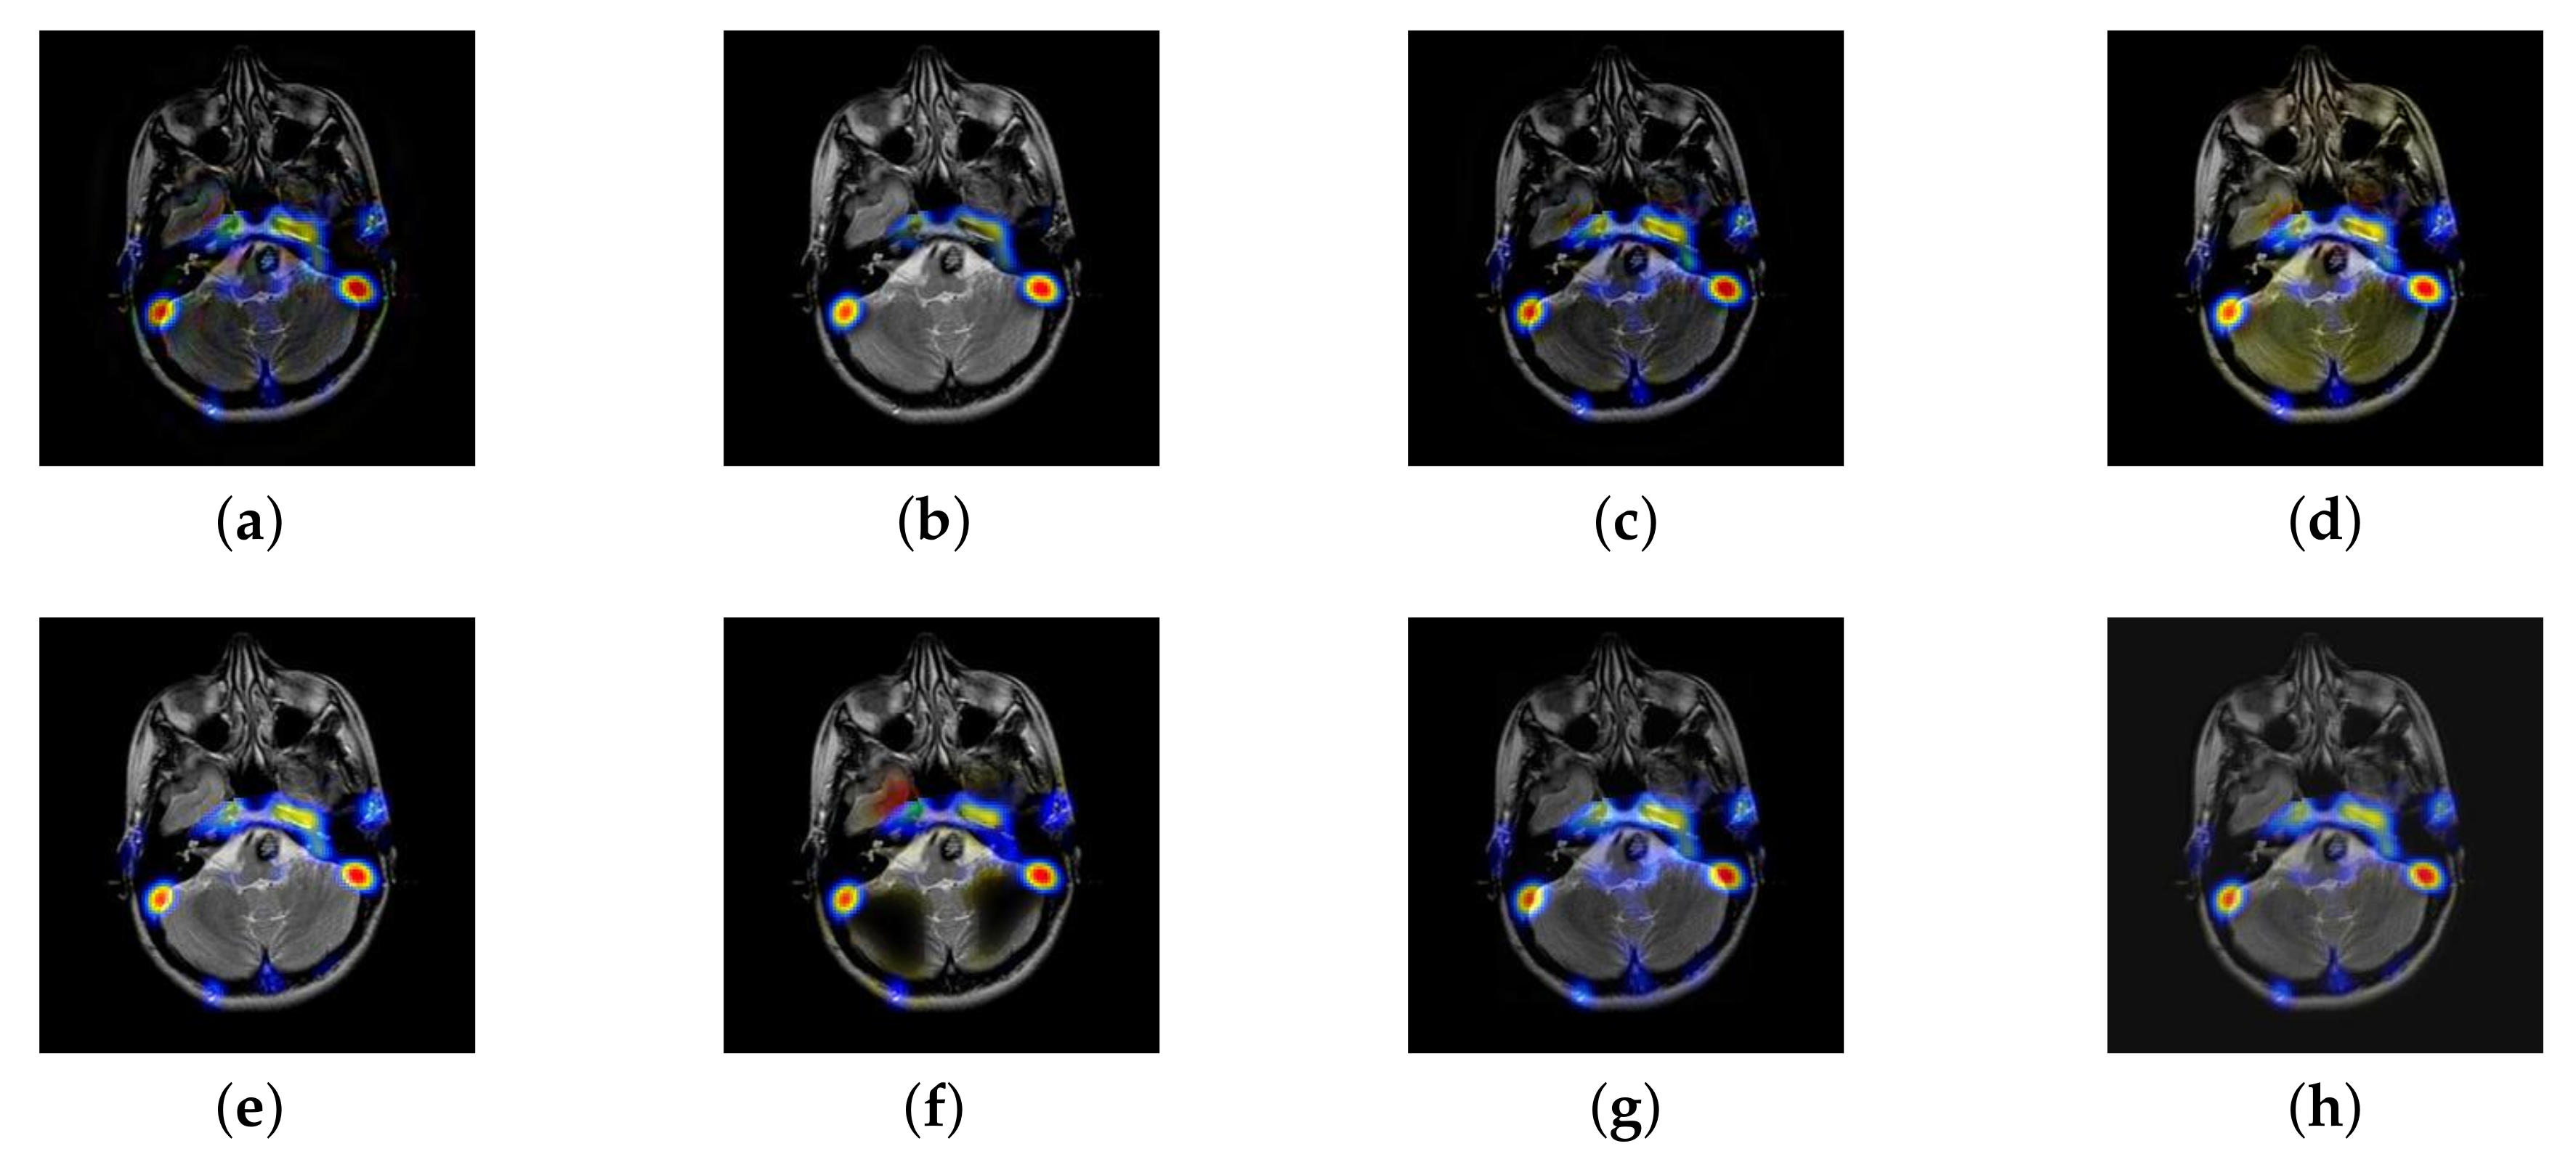

In this section, there are four multi-modal image sets and each set is consist of MRI image and SPECT image that are corresponding to the sanme location slice of the brain as shown in Figure 7. Among them, Figure 7e,f are captured from patients who have suffered a subacute stroke. Figure 7a–d,g,h are captured from patients who have brain tumor. The fused images with different fusion methods based on DTCWT, NSCT, GFF, LPSR, IGM, DDcGAN, FusionCNN, and the proposed methods are shown in Figure 8, Figure 9, Figure 10 and Figure 11. It can be seen that the fused images obtained by LPSR and FusionCNN algorithm have serious color distortion. Based on DTCWT and NSCT algorithm, the fusion image structure information is not obvious. The fused images obtained by GFF and IGM algorithm contain almost no color information, which is not conducive for doctors to make correct diagnosis. The image obtained by the DDcGAN algorithm saves the color information in the SPECT to a great extent; however, the brightness of the fused image is too large, which causes the image to have no sense of hierarchy and the contrast to decrease. By comparing with other algorithms, we find that our algorithm has good color retention effect, clear structure information, moderate brightness, and no artifacts.

Figure 8.

Fused medical images obtained by different algorithms (Figure 7a,b): (a) dual tree complex wavelet transform (DTCWT), (b) guided filtering fusion (GFF), (c) non-subsampled contourlet transform (NSCT), (d) Laplacian pyramid sparse representation (LPSR), (e) internal generative mechanism (IGM), (f) Fusion convolutional neural network based (FusionCNN), (g) dual-discriminator conditional generative adversarial network based (DDcGAN), and (h) FusionNet.

Figure 9.

Fused medical images obtained by different algorithms (Figure 7c,d): (a) DTCWT, (b) GFF, (c) NSCT, (d) LPSR, (e) IGM, (f) FusionCNN, (g) DDcGAN, and (h) FusionNet.

Figure 10.

Fused medical images obtained by different algorithms (Figure 7e,f): (a) DTCWT, (b) GFF, (c) NSCT, (d) LPSR, (e) IGM, (f) FusionCNN, (g) DDcGAN, and (h) FusionNet.

Figure 11.

Fused medical images obtained by different algorithms (Figure 7g,h): (a) DTCWT, (b) GFF, (c) NSCT, (d) LPSR, (e) IGM, (f) FusionCNN, (g) DDcGAN, and (h) FusionNet.